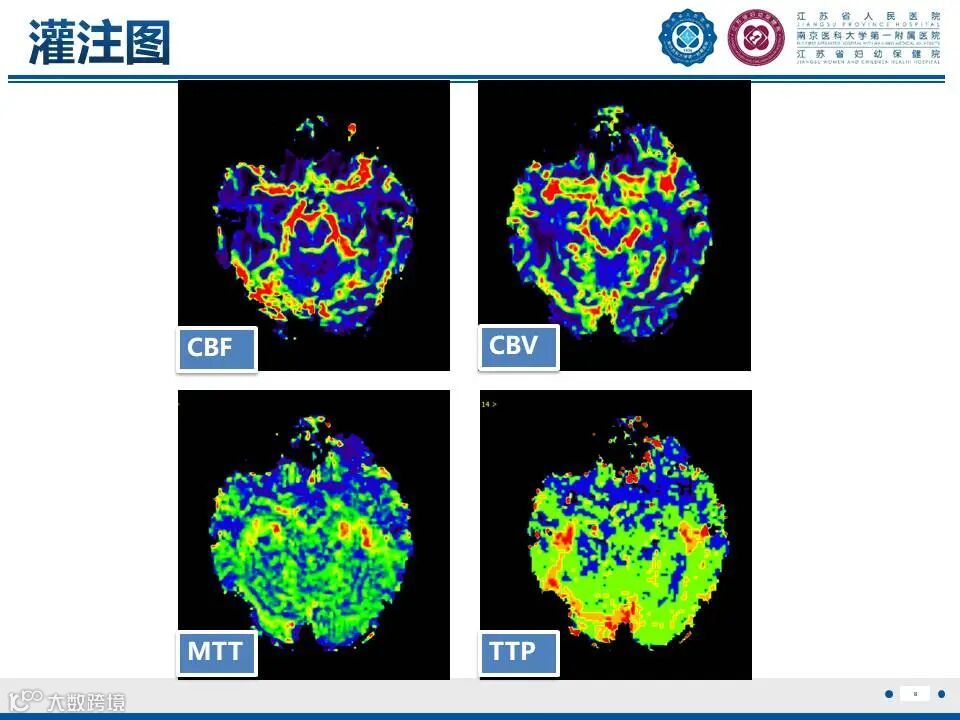

来源:江苏省人民医院放射科